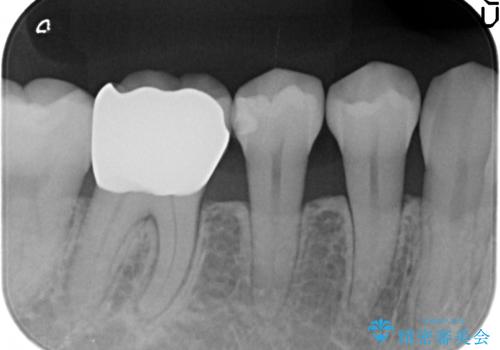

- 右下6番目の銀歯が気になるのでセラミックにしたいといらっしゃった方の症例です。

銀歯及び虫歯を除去後、オールセラミッククラウンによる補綴を行いました。

今回用いたオールセラミッククラウンはジルコニアフレームという白い素材の上にセラミックを盛っているため、審美性が非常に高いのが特徴です。

また、ジルコニアは人工ダイヤモンドの材料にも使われているほど高い強度を持っており、そのためオールセラミッククラウンは審美性だけでなく、奥歯やブリッジの補綴も可能とするクラウンです。